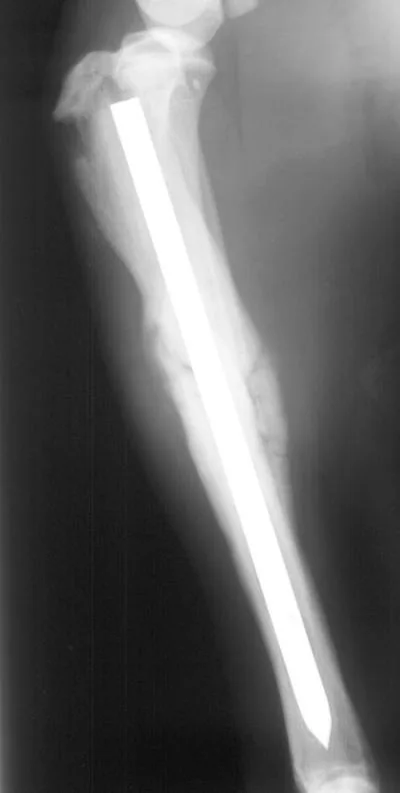

External Fixators

External fixators are often used for biologic management of fractures because of the lower implant cost and relative ease of application. External fixators can be used with closed or open reduction of the fracture. When applied correctly, vascular supply of the fracture fragments can be effectively preserved. Linear external fixators (Figures 3A, B) are most commonly used, but circular fixators are gaining popularity and have advantages for some fracture types. This tibia and fibula fracture achieved bony union in 7 weeks.